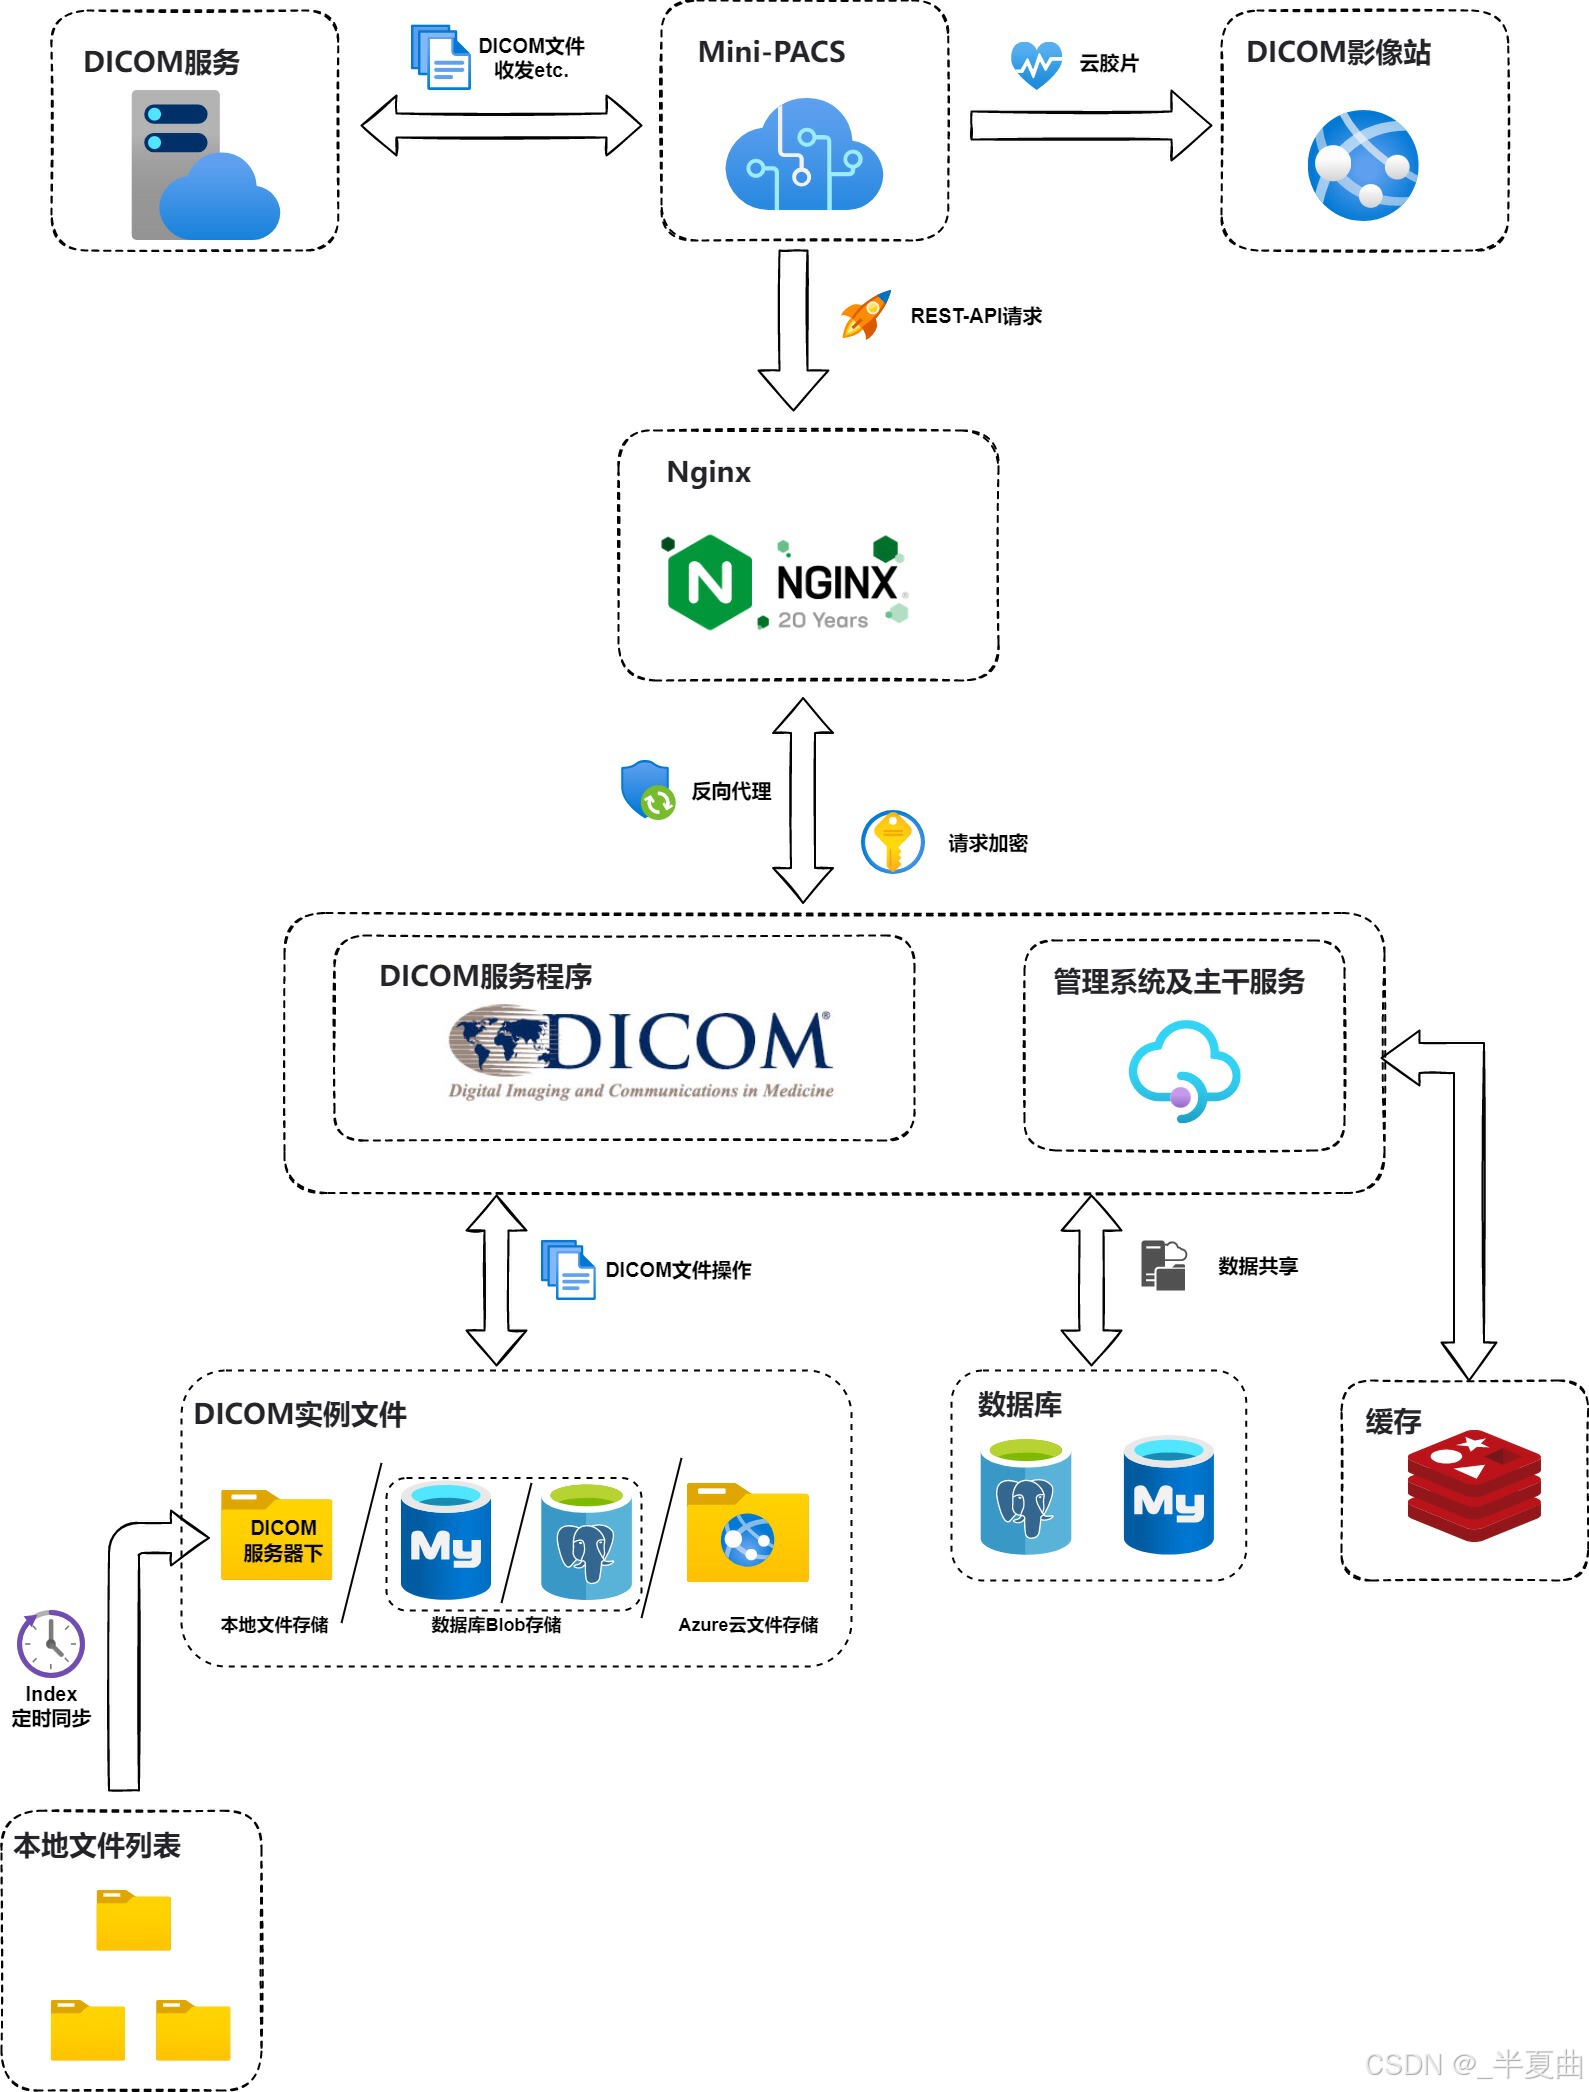

系统架构:

基于B/S架构的 Web版 Mini PACS 系统,应用开源主流Dicom服务器(站在巨人的肩膀上💪),后端采用 JAVA,利用SSM 等主流框架,前端采用 Vue2、React 框架开发,数据库采用 MySQL、Redis 。主要实现 Dicom 文件接收与传输、云胶片、CD/DVD 刻录、在线报告、数据分析等功能。目前已打通 Dicom 文件于系统中的数据流,数据文件可通过接收 Dicom 服务节点获取,也可手动上传文件,并且可将患者检查的 Dicom 文件传输至系统中动态配置的 Dicom 服务器;实现在线云胶片功能,可在线查看与操作医学影像图像等功能。